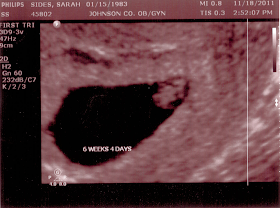

Craig ran another half-marathon (and beat his earlier time) and we planned a big Chiefs tailgate. Craig also started the remodel of our upstairs/guest bathroom. But the best part of October? Learning we were going to be parents!!!!